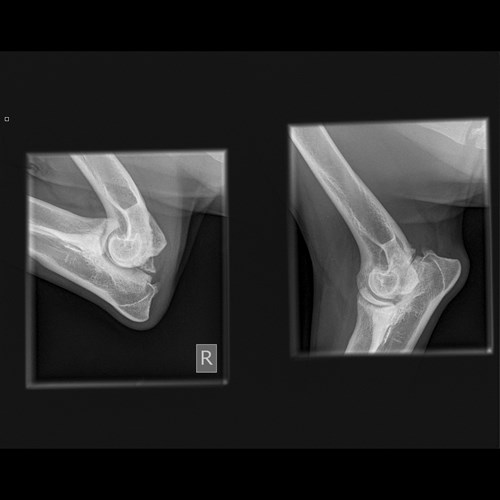

My mom then noticed after a few days she could hear clicking in my elbows every now and again when I moved so decided to take me for some xrays to make sure they were ok.

Sadly the vet gave my mom bad news. I need surgery as soon as possible to remove a piece of loose bone in both my elbows else I am going to become poorly very quickly wihich she does not want me to do.